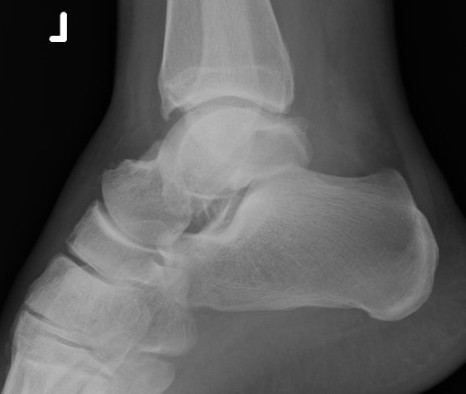

Canale view

- evaluates talar neck

- foot everted 15 deg

- look for medial shortening / varus

Xrays

| AP | Lateral | Canale View |

|---|---|---|

| Entry point of the screws |

Evaluate neck reduction

|

Evaluates the neck reduction |

Lateral off articular surface Medial through articular cartilage |

Depth of screws |

Beam angled 75o to foot Foot 15o pronated |